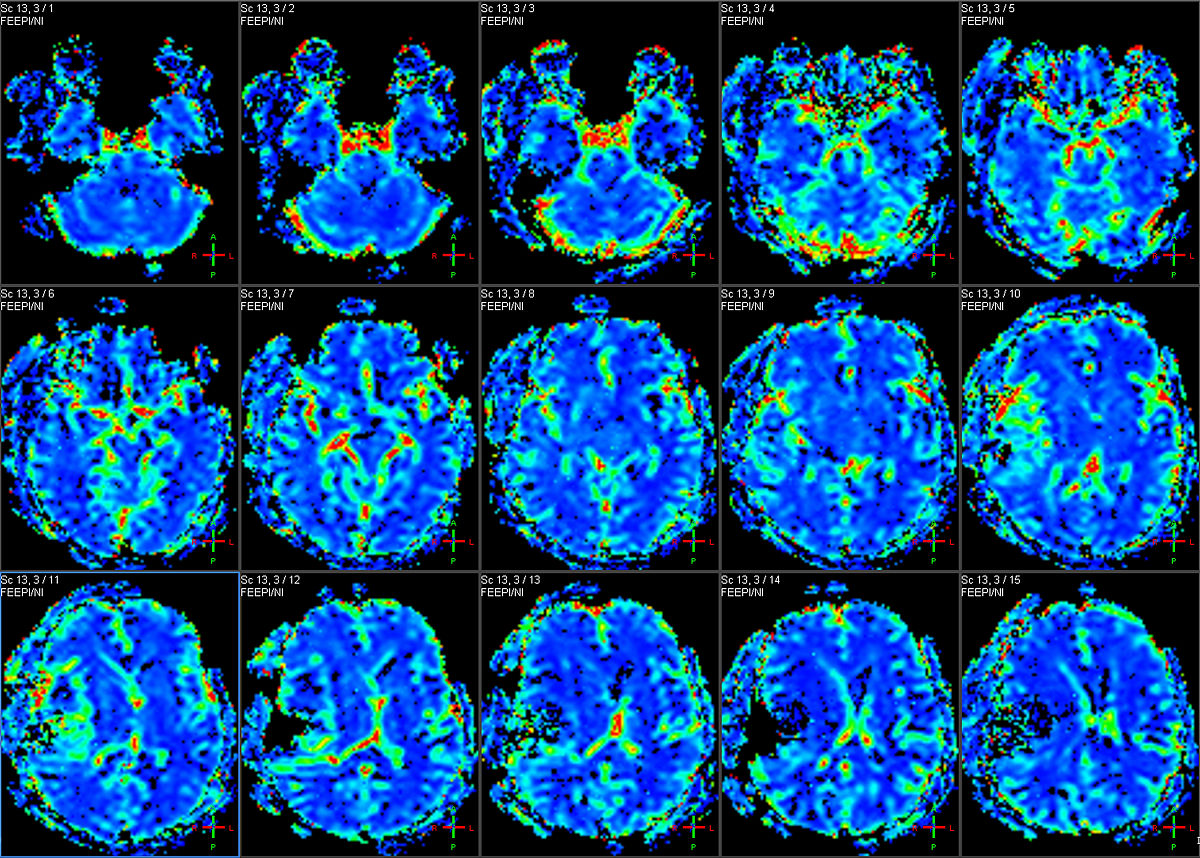

第三页: 标题:PET技术应用领域 关键要点:肿瘤诊断、神经精神疾病、心脑血管疾病 正文内容: PET技术在医学领域有广泛的应用,主要包括肿瘤诊断、神经精神疾病、心脑血管疾病等。在肿瘤诊断方面,PET技术可以通过标记葡萄糖等物质来检测肿瘤细胞的活动程度,辅助诊断和治疗。在神经精神疾病方面,PET技术可以通过标记多巴胺等物质来检测大脑神经元的活动情况,辅助诊断和治疗。在心脑血管疾病方面,PET技术可以通过标记氧气等物质来检测心脏、脑血管的代谢情况,辅助诊断和治疗。

第四页: 标题:PET技术优点 关键要点:高灵敏度、高空间分辨率、多元信息 正文内容: PET技术相比于其他成像技术具有高灵敏度、高空间分辨率、多元信息等优点。高灵敏度指PET技术可以检测到极少量的放射性标记物质,使得诊断精度更高。高空间分辨率指PET技术可以将人体内部器官、组织等细小结构进行成像,使得诊断更加准确。多元信息指PET技术可以通过标记不同的物质来获取不同的信息,如代谢、血流等,使得诊断更加全面。